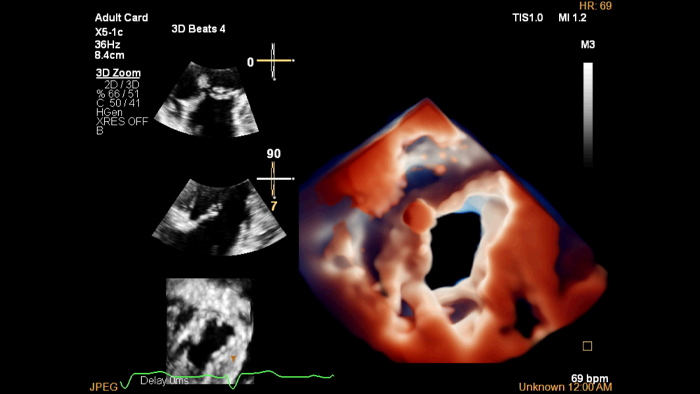

Photorealistic imaging in 3D echocardiography

A virtual light source highlights structures and facilitates depth perception for enhanced interpretation of heart disease images.